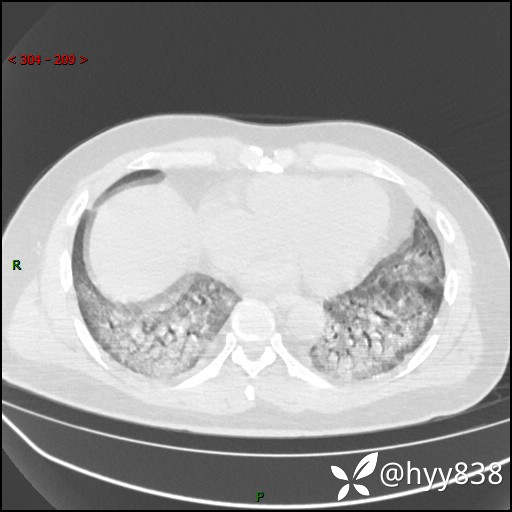

第二次CT(7天后)